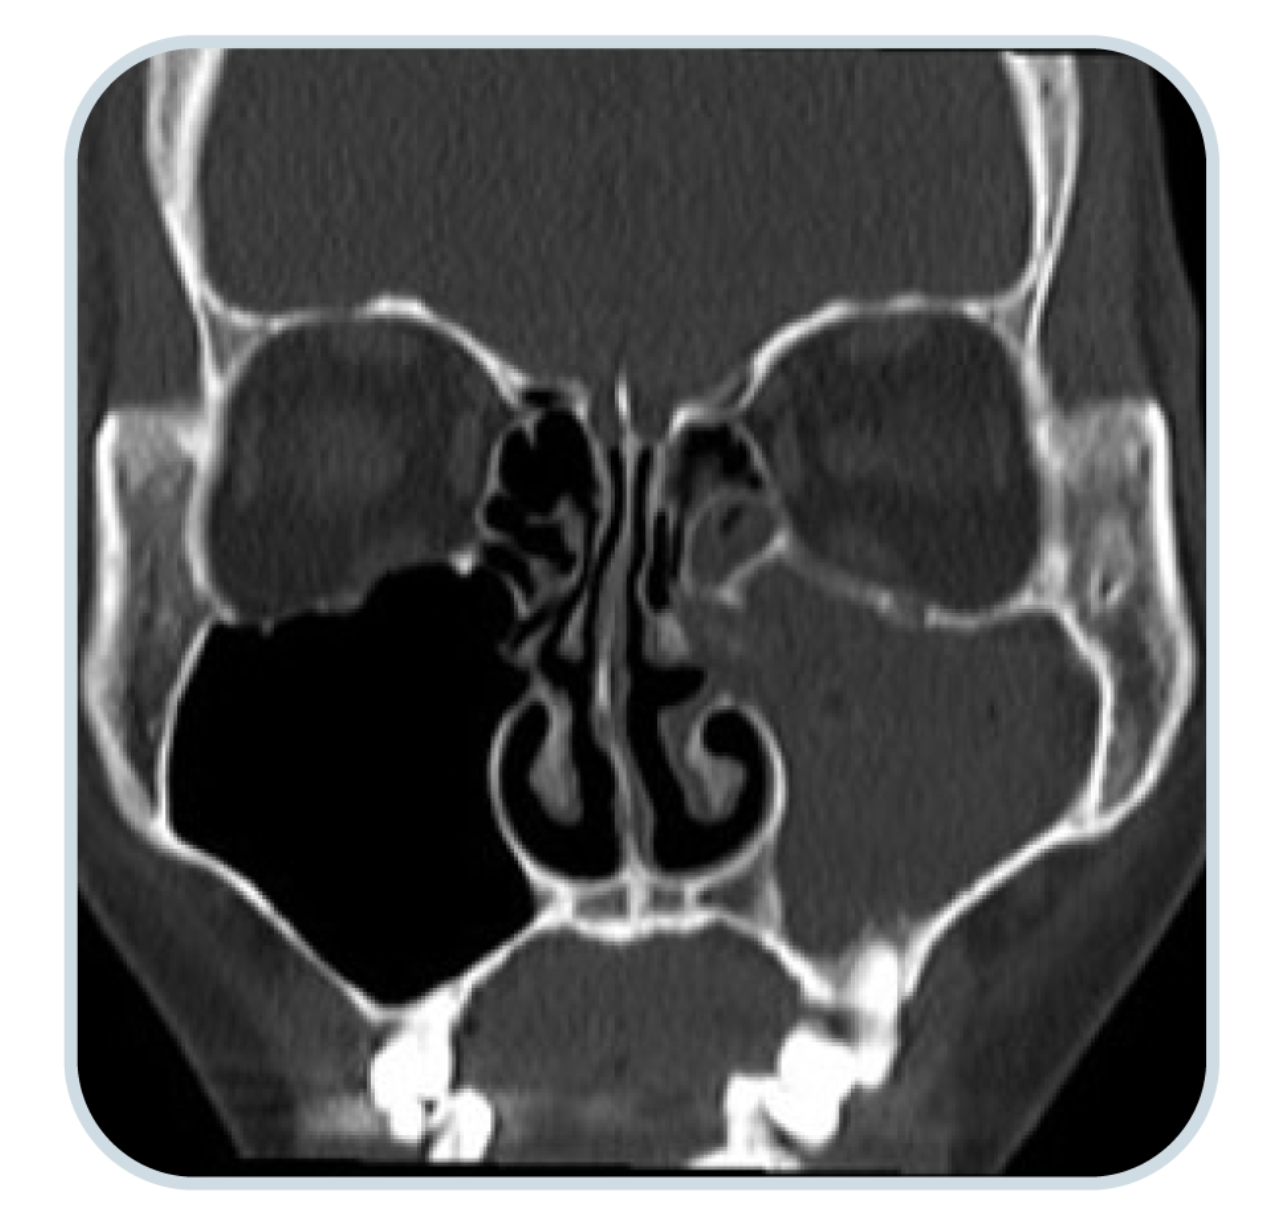

鼻竇電腦掃描

觀察鼻竇內的積液狀況以及鼻腔結構是否正常,並可藉此得知鼻竇內是否有鼻瘜肉、黏液分泌程度和發炎情況等細節。